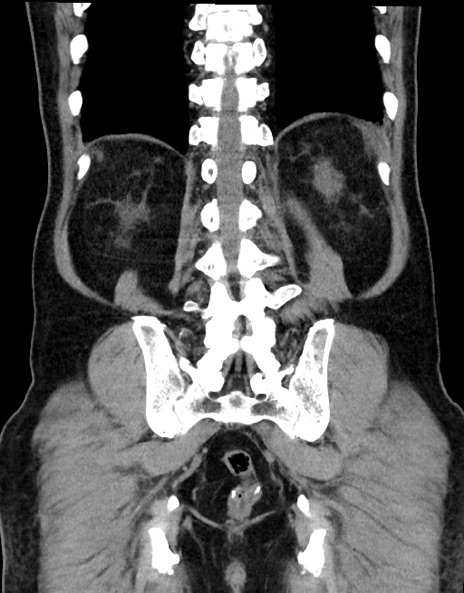

症例15(冠状断像)

【症例】70歳代男性

【主訴】腹痛

【現病歴】今朝から腹痛あり。全体的に痛い。特に左上の方。排ガスが今日はない。冷や汗が出る。

【既往歴】直腸癌術後

【身体所見】左側腹部〜上腹部に圧痛あり。腹膜刺激症状明らかなではない。軽度反跳痛。左下腹部に術後瘢痕あり。

【データ】WBC 7700、CRP 0.02